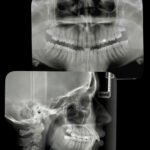

• Ortopantomogram (panoramska snimka): Cjelovit prikaz čeljusti i zuba, potreban za prvi pregled, vađenje zuba kod oralnog kirurga, za ortodonciju i čitav niz ostalih stanja i bolesti zubi i usne šupljine te se smatra najčešćom snimkom digitalne zubne dijagnostike. Ortopan snimka u svakodnevnoj praksi među doktorima dentalne medicine je sinonim za ZUBNI RENDGEN

Primjer jednog ortopana